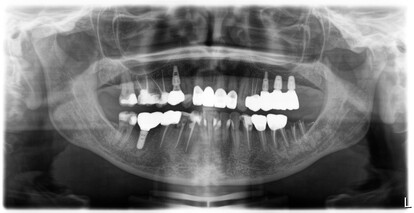

”Personalmente rimarrò con il dubbio continuando ad utilizzare questa geometria nei casi in cui l’atrofia ossea nel mascellare superiore mi permetterà di ottenere un’altezza sufficiente per l’inserimento e stabilizzazione implantare, senza ricorrere a tecniche rigenerative a carico del seno mascellare. Con l’impianto ADVANGTB SINUS LIFT, un nuovo caso è stato trattato per continuare a sfruttare questa geometria implantare, che ha già fornito risultati soddisfacenti. Si vogliono valorizzare le proprietà osteogenetiche che si attivano in seguito allo scollamento della membrana di Schneider, sfruttando il suo naturale letto di appoggio osseo. In questo caso, tre impianti ADVAN sono stati inseriti in una paziente con volumetrie ossee diverse (sito-specifiche), nel secondo quadrante (arcata superiore sinistra).

Questo case report mette in evidenza il ruolo della geometria implantare nella gestione dell’atrofia ossea, offrendo un’alternativa meno invasiva rispetto ai tradizionali rialzi di seno mascellare. L’implantologia risulta essere la scelta migliore sia clinicamente che biologicamente per una riabilitazione protesica fissa. Questa opportunità diventa ancora più convincente se non vi è presenza di pilastri naturali. La macrogeometria dell’impianto GTBSINUS LIFT di Advan è volta a garantire una stabilità primaria anche in condizioni di atrofia e, o di scarsa densità ossea, che spesso caratterizzano le regioni posteriori del mascellare.

Gli impianti ADVAN si distinguono come una soluzione ottimale, garantendo un’ampia possibilità di scelta e un inserimento efficace in diverse tipologie di osso, sia per densità che per altezza, anche nei casi in cui l’atrofia del mascellare superiore potrebbe rendere altrimenti necessarie procedure chirurgiche più invasive.